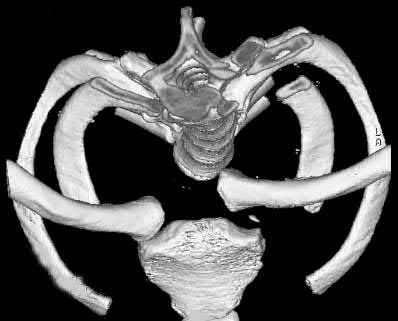

A poly-trauma patient presents hemodynamically unstable with an anteroposterior compression (APC-III) pelvic ring injury. A circumferential pelvic binder is requested to reduce pelvic volume and control hemorrhage. To be anatomically effective, the binder must be centered precisely over which of the following landmarks?

Explanation

For optimal mechanical advantage and effective reduction of an 'open book' pelvic fracture (APC type), a pelvic binder must be applied directly over the greater trochanters of the femurs. Applying it higher, such as over the iliac crests, is a common error that fails to adequately close the pelvic ring and can paradoxically open the true pelvis.